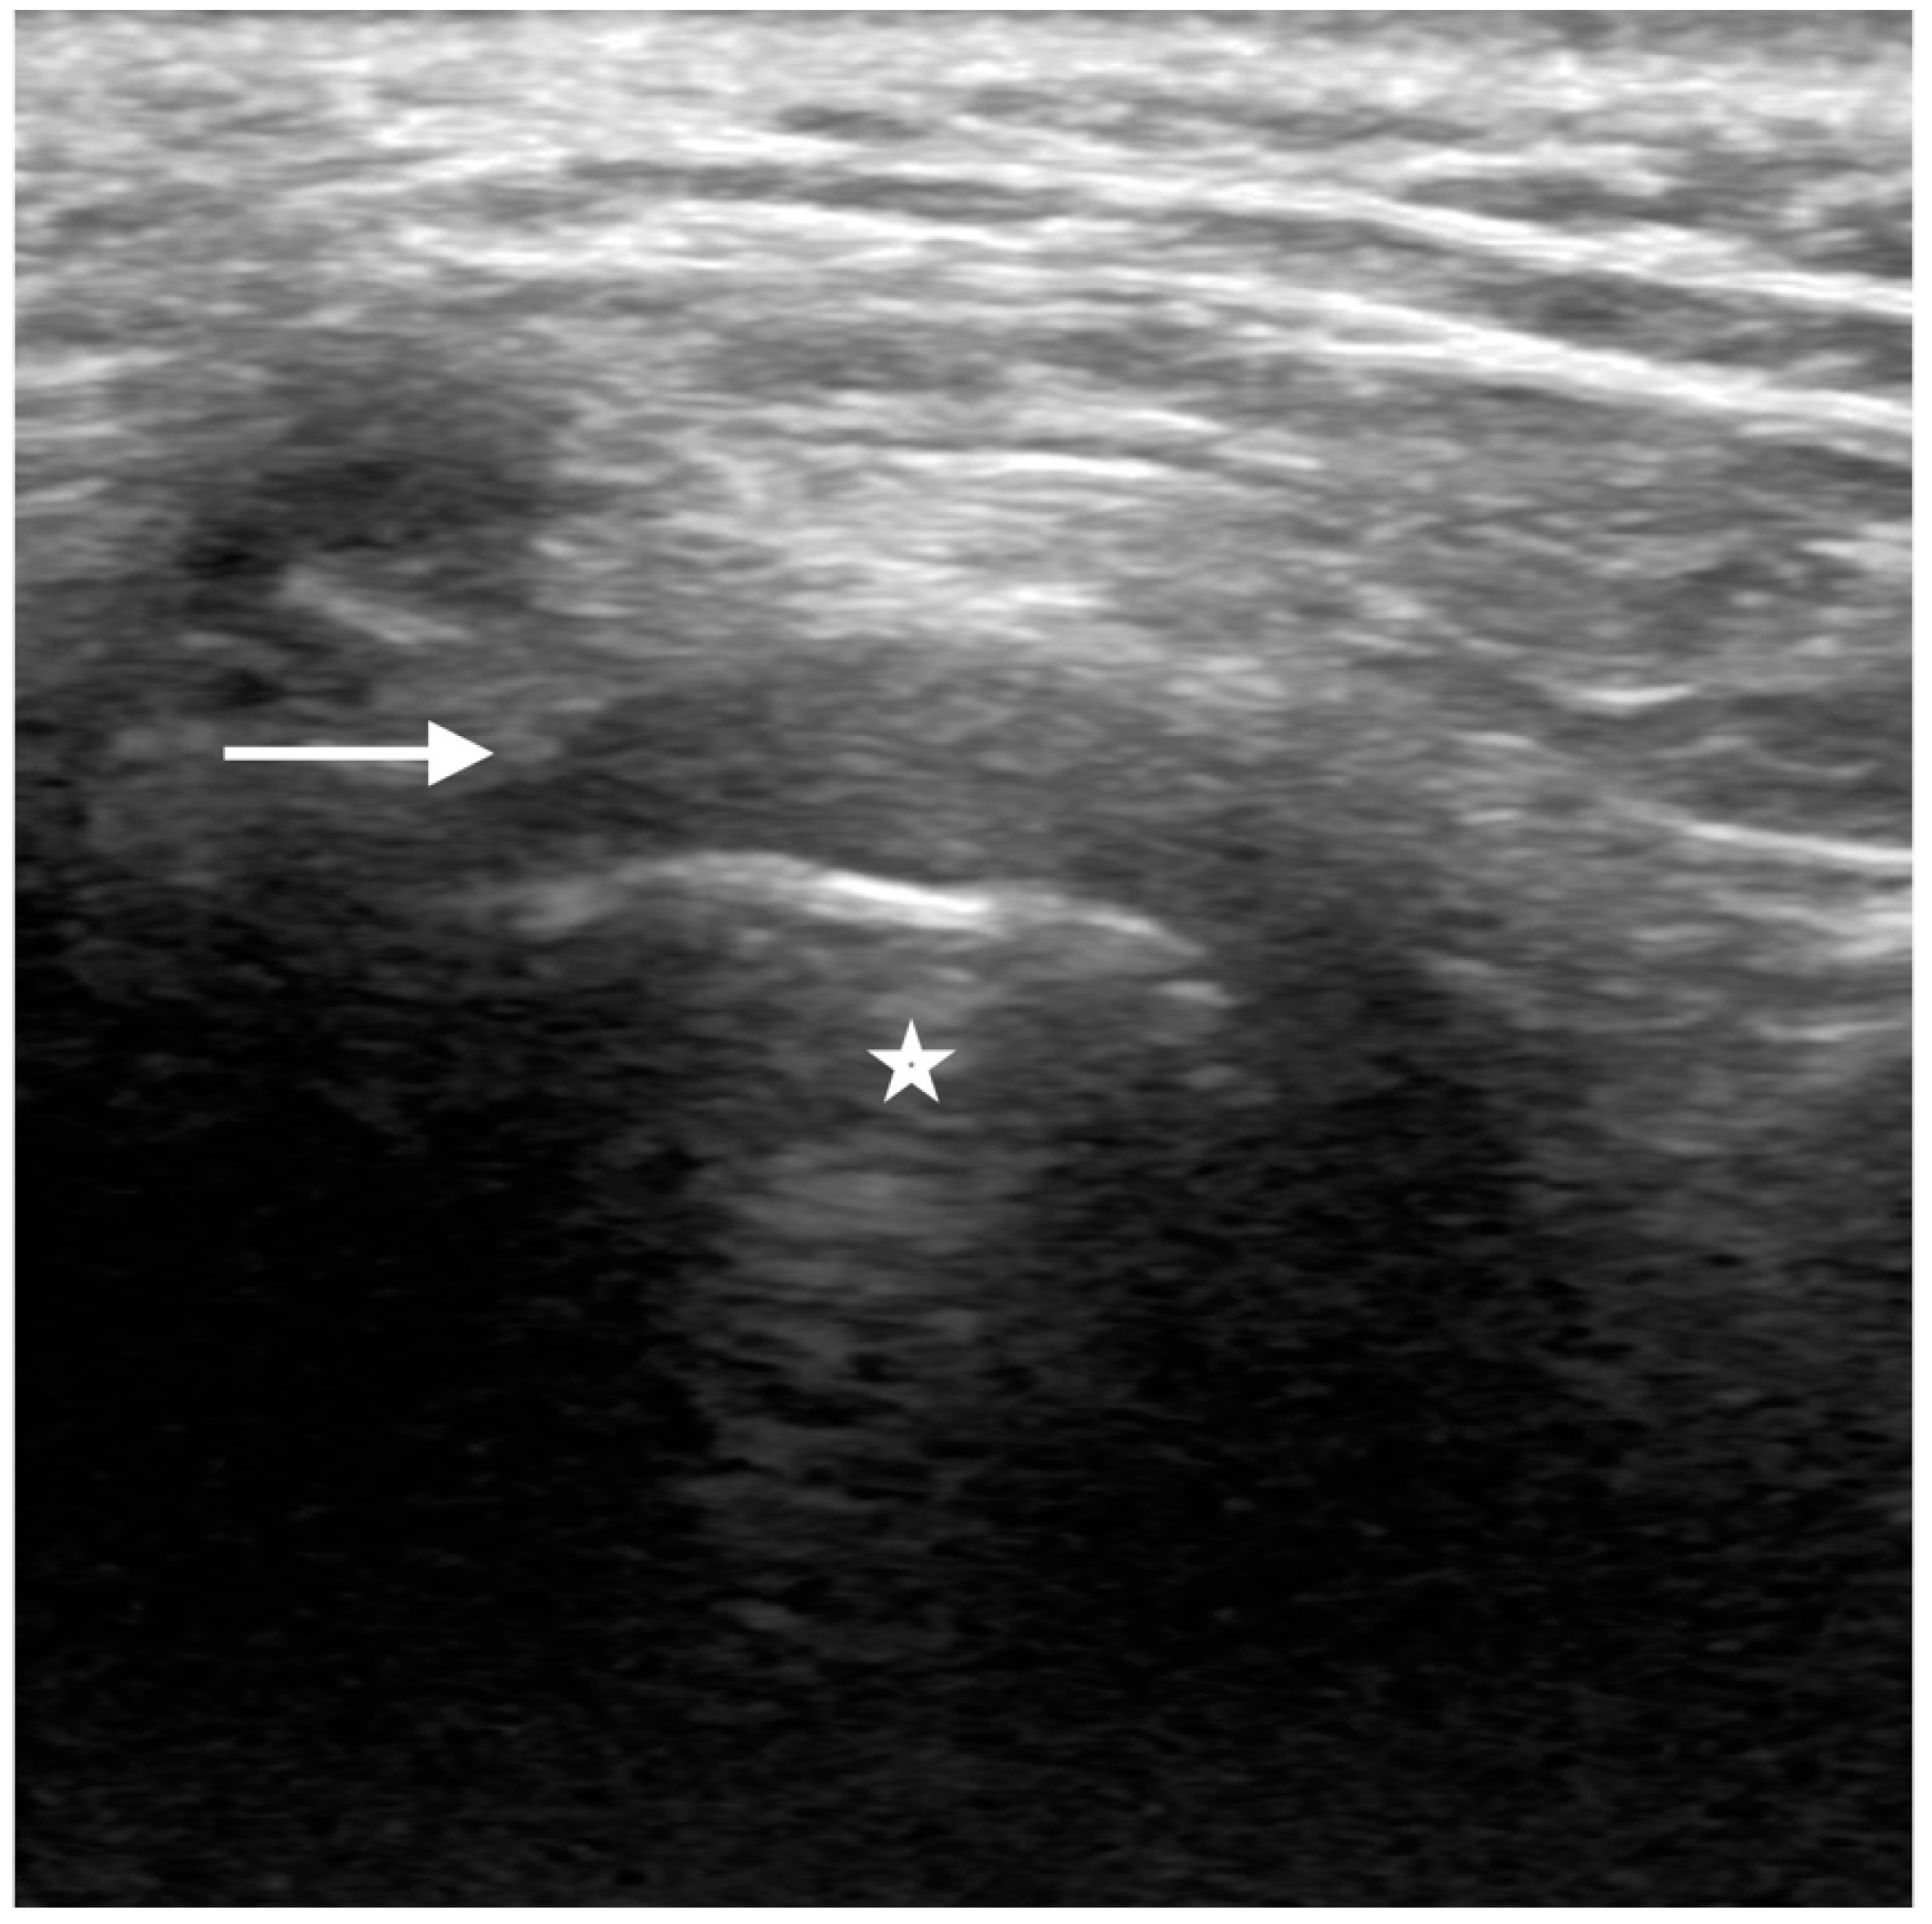

Figure 3. Normal ultrasound of the articular disc. Sonographic images of the TMJ with the probe longitudinal to the articular disc on closed mouth views demonstrate the normal hypoechoic appearance of the mandibular condyle (star), with a rim of the hyperechoic cortex. The articular disc (straight arrow) demonstrates the normal inverted c-shaped morphology and hypoechogenicity, situated just superior to the condylar cortex.